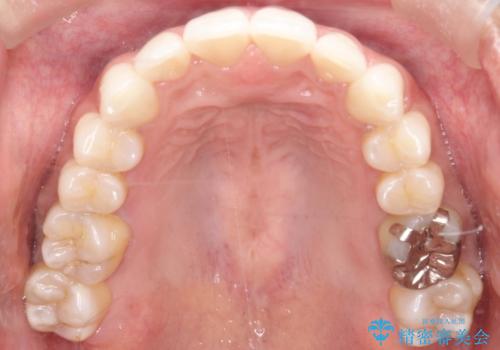

【インビザライン】前歯の凸凹をIPRで改善

- 前歯の凸凹を主訴に来院されました。

前歯を並べるために歯と歯の間にヤスリを入れてわずかに歯を削ることでスペースを確保しています。

歯と歯の間にヤスリを入れてわずかに歯を削ることでスペースを確保する処置をIPRと呼びます。

当院では拡大鏡を用いて丁寧に処置することで歯冠形態を損なわずに行うことができます。